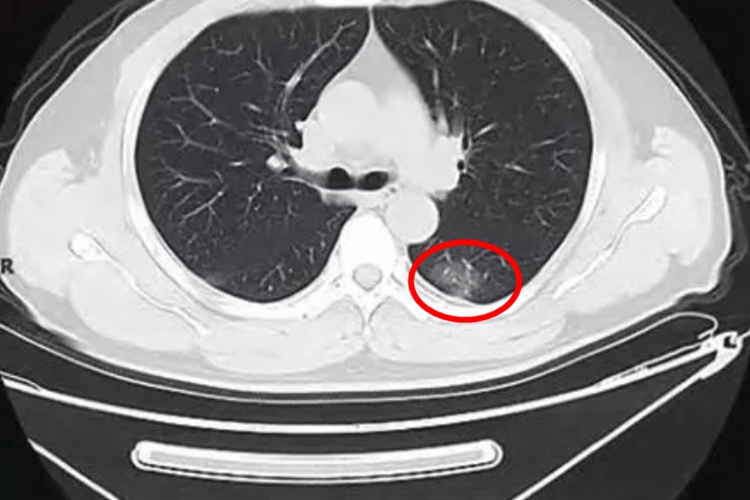

磨玻璃肺部结节是一个影像学概念,指的是在肺部CT检查中呈现为雾状密度阴影的结节。对于3mm大小的磨玻璃结节,大多数情况下并不严重。这种微小的结节很可能是良性的,由炎症、感染等因素引起,不会对身体造成明显的损害,也无需特殊治疗。

虽然3mm磨玻璃结节多为良性,但仍存在恶性病变的可能性。因此,一旦发现此类结节,建议遵医嘱进行定期复查,以监测结节的生长情况。如果在复查过程中发现结节明显增大、形态改变或出现其他异常情况,应及时就医进行进一步检查和治疗。